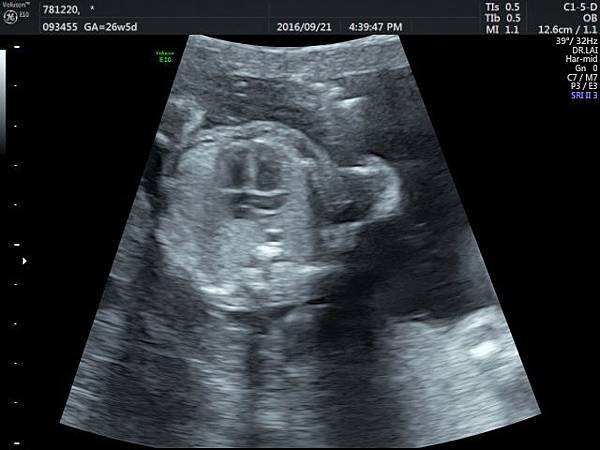

2016. 9. 21.

賴錫鉅

2016年9月21日幫一位懷孕26歲懷雙胞胎的孕婦看胎兒心臟超音波,孕婦目前26週,雙胞胎大小相差四週,高層次超音波除了小的胎兒臍動脈血流有問題之外,沒有其他異常發現,經過我的檢查,我的診斷是小的胎兒有持續性左側上腔靜脈(附圖1~5)。

正常情況左側的上腔靜脈在胚胎發育過程應該要退化,左側頭頸部的靜脈回流是流向右側的上腔靜脈再回到右心房,而持續性左側上腔靜脈是這條血管沒有退化繼續存在,它的血流一般會流入左心房背部的冠狀竇(coronary sinus)再經由冠狀竇回到右心房,因為最終都是回到右心房,理論上沒有什麼問題,只是為何它會不退化呢?是否有什麼因素造成它不退化這才是重點所在,所以做染色體基因檢查的理由就是找出是否有原因。

因為冠狀竇變大,超音波影像常被誤解為心房中隔缺損,兩者的預後差很多,鑑別診斷需要經驗,我常跟孕婦說,如果只給我10分鐘檢查一位胎兒,我會選擇看胎兒心臟,因為心臟就像一部車子的引擎,胎兒先天性心臟病常會合併染色體基因的問題,藉由心臟檢查,可以縮小範圍。